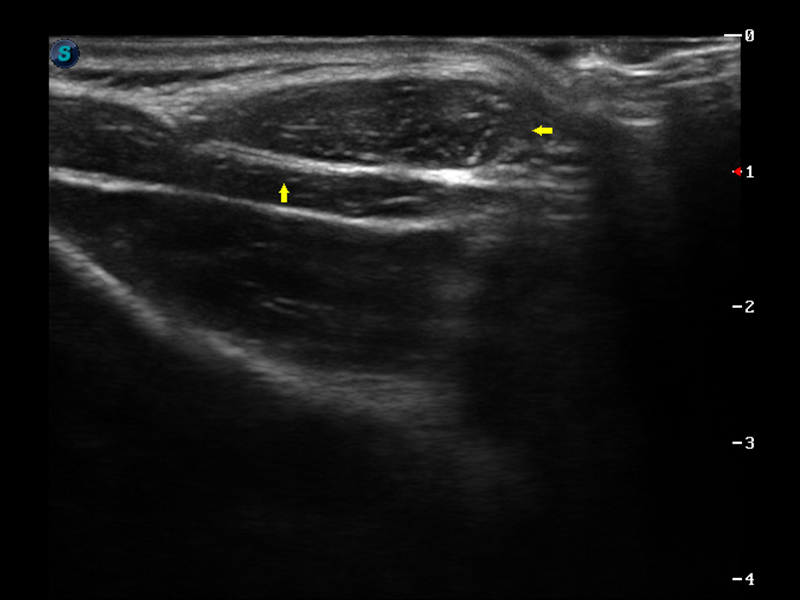

S9便携式彩色多普勒超声诊断仪是米兰官方网站研发的高端便携彩超设备,外观设计新颖、产品性能卓越。S9在便携超声领域采用了突破传统的触摸屏交互设计,并以先进的软件硬件技术和设计理念,为您带来清晰的图像质量、稳定的工作性能和便捷的操作体验。

μ-Scan微米成像